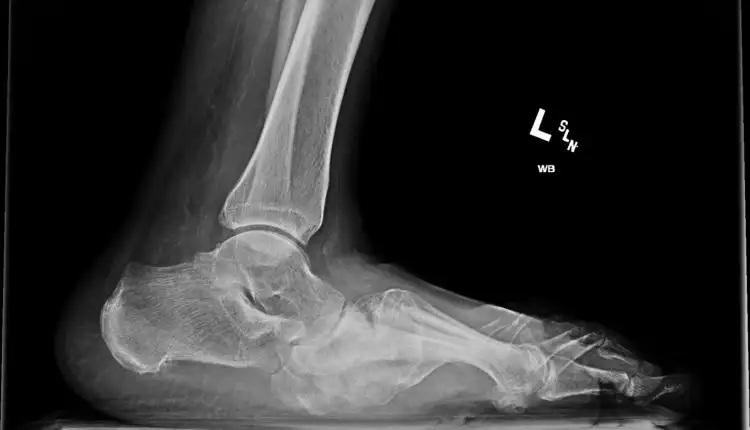

Tempat Pengobatan Kanker Depok dan Tangerang – Charcot joint biasanya dikenal sebagai neuropati Charcot adalah kondisi yang terjadi ketika kerusakan saraf menyebabkan kerusakan pada sendi dan tulang di sekitarnya. Kondisi ini dapat mempengaruhi siapa saja, tetapi lebih umum terjadi pada orang yang menderita neuropati diabetik. Untuk itu, supaya tidak terjadi komplikasi yang serius lebih baik membawanya pergi ke tempat pengobatan charcot joint atau sendi charcot di Bangkinang. Karena tempat pengobatan yang satu ini telah mampu menyembuhkan berbagai jenis penyakit juga termasuk charcot joint salah satunya.

Pada tahap awal, Charcot joint mungkin tidak menimbulkan gejala atau hanya menimbulkan gejala ringan seperti kemerahan, bengkak, atau rasa sakit di sekitar sendi yang terkena. Namun, jika tidak diobati, kondisi ini dapat berkembang menjadi lebih parah dan menyebabkan deformitas permanen pada sendi, serta kesulitan dalam berjalan dan bergerak.

Charcot joint dapat menyebabkan deformitas dan gangguan mobilitas yang signifikan, sehingga pengobatan yang tepat sangat penting untuk mencegah komplikasi yang lebih serius. Seperti misalnya dengan mendatangi tempat pengobatan charcot joint atau sendi charcot di Bangkinang menggunakan metode penyembuhan terapi. Sebab, terapi dinilai salah satu metode penyembuhan yang lebih aman dan efektif untuk dilakukan pada pasien.